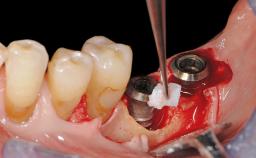

A 37-year-old male patient was referred to the Department of Periodontology at the University of Bern, Switzerland, by a private dentist. Tooth 21 had been lost due to trauma and had been replaced with an implant and a cemented single crown. The tapered-effect tissue-level implant had a diameter of 4.1 mm, a length of 12 mm, and a sandblasted and acid-etched (SLA) surface (Straumann Dental lmplant System; Institut Straumann AG, Basel, Switzerland). The metal-ceramic crown had been cemented permanently, leaving a submucosal gap between the implant shoulder and the crown margin. Absence of marginal bone loss apical to the polished transmucosal neck of the implant could be observed .